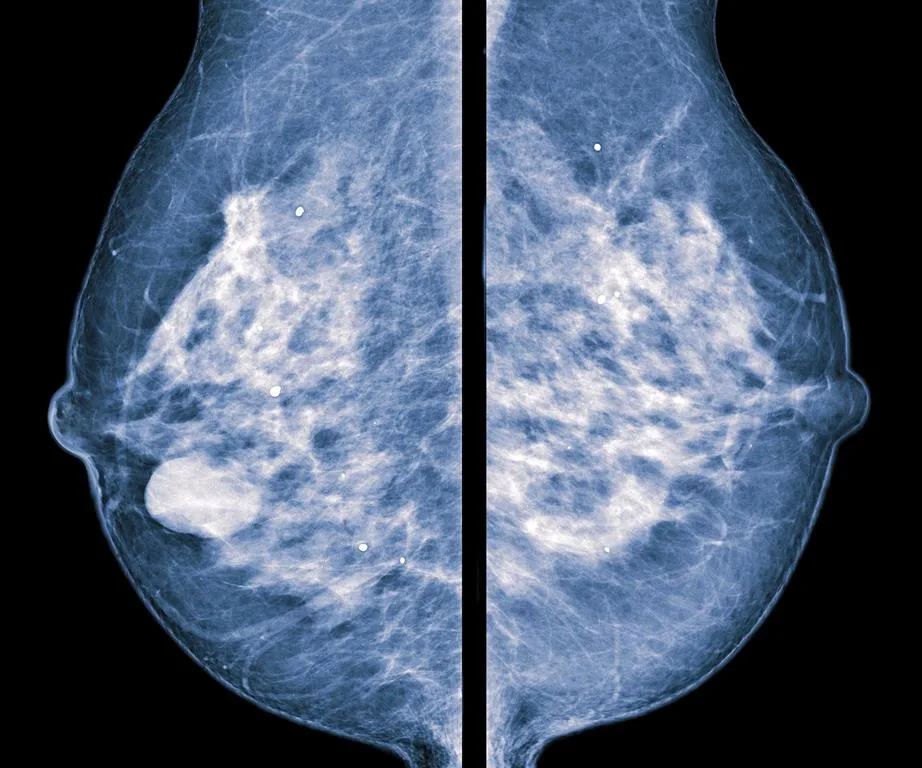

The breast density of these women was measured using mammograms, and categorised into four groups:

A: breasts composed almost entirely of fat;

B: participants with scattered dense tissue but mostly fat;

C: those with moderately dense tissue, and

D: women with dense tissue that makes up around 75 per cent of the breast.

Both breast tissue and cancer appear white on a mammogram

Cancer and breast tissue appear white on mammograms, which makes a radiologists job all the more tricky.

Fat on the other hand, appears dark, making it easier to spot cancers against it.